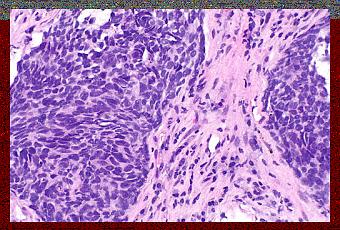

Cancer du Poumon Non à Petites Cellules.

Source: https://commons.wikimedia.org/wiki/File:Non-small_cell_lung_carcinoma_--_high_mag.jpg